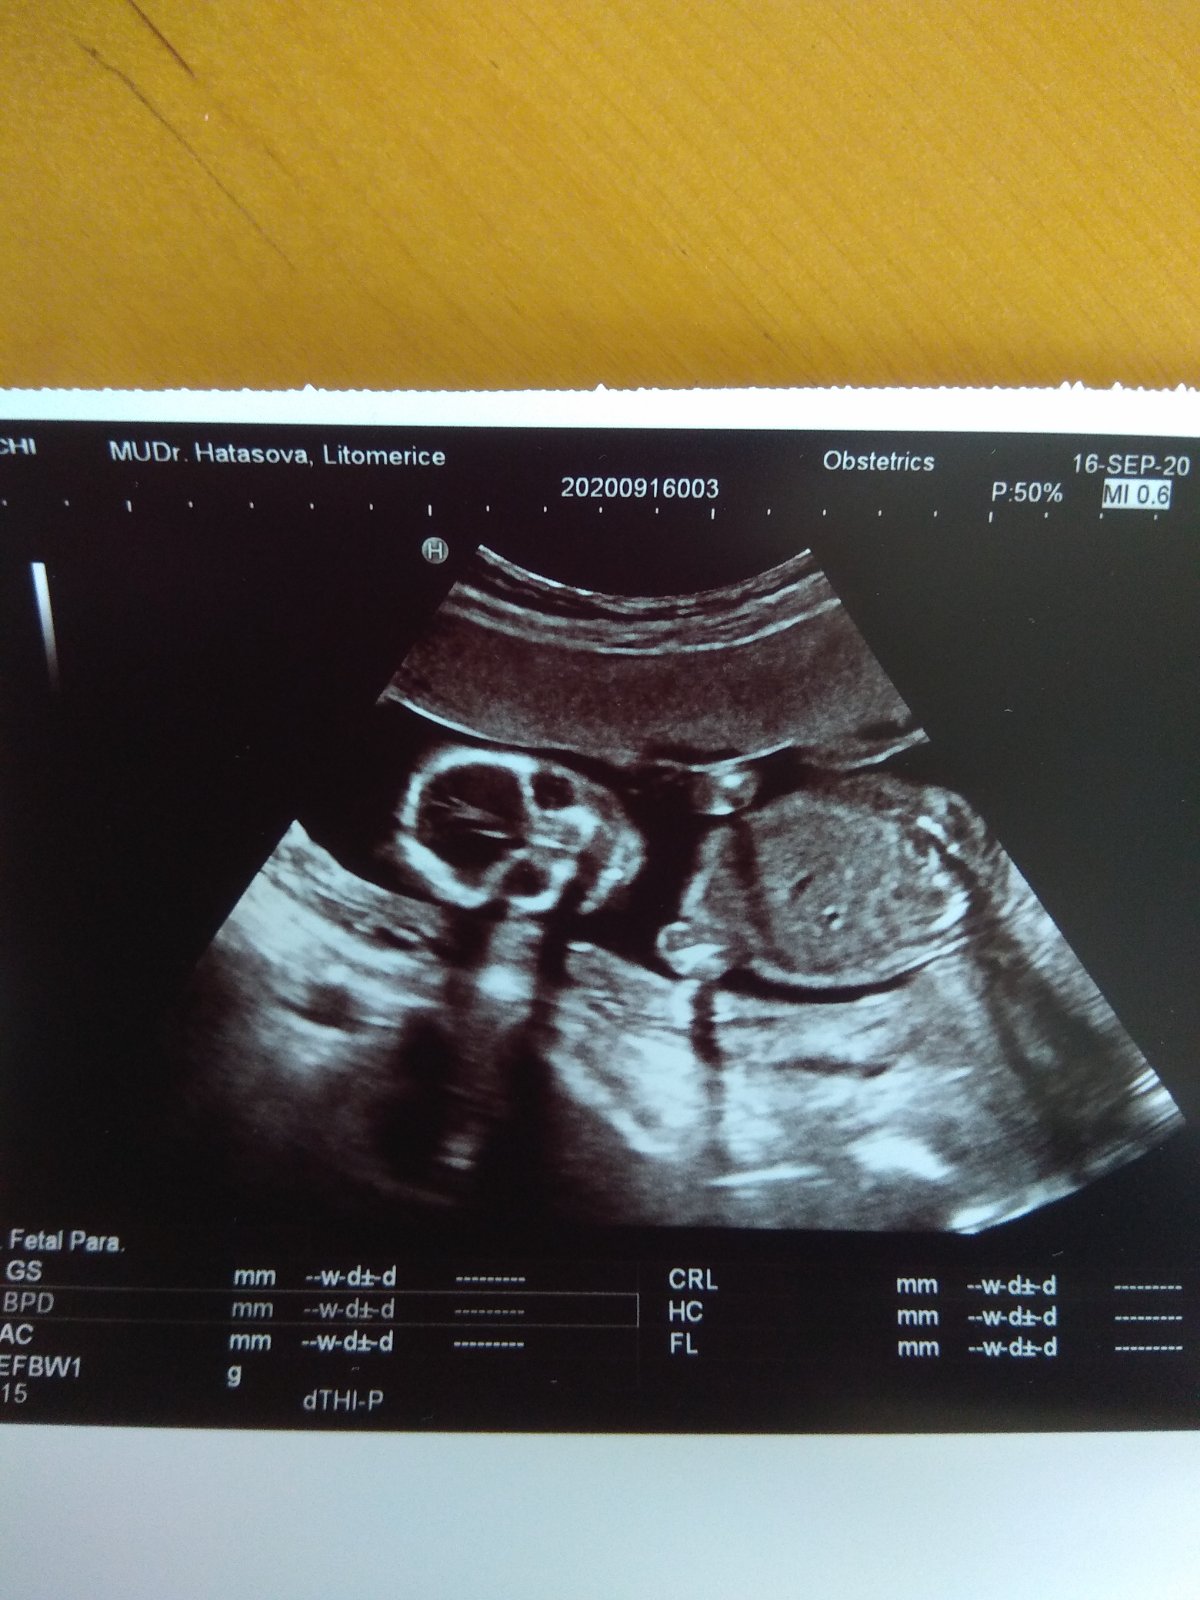

Foto z ultrazvuku. Holčička nebo klučík?

Hezký večer, dnes jsme byli na screeningu v prvním trimestru, paní doktorka nám řekla pohlaví s jistotou 90%, nicméně prý už se takhle jednou sekla, tak by mě, čistě ze zvědavosti, zajímalo, co myslíte vy? Mě to podle toho co jsem na internetu vyčetla sedí s paní doktorkou, ale víte jak, sem baba zvědavá 🙂

@rennye pan doktor rekl, ze nejspis kluk podle screeningu ve 13 tt😄ale uvidime!😃

@rennye takze nakonec je to kluk 😄💙

@mikejla_a holčička potvrzena na 100% na ultrazvuku ve 21tt 🙂 Děkuji